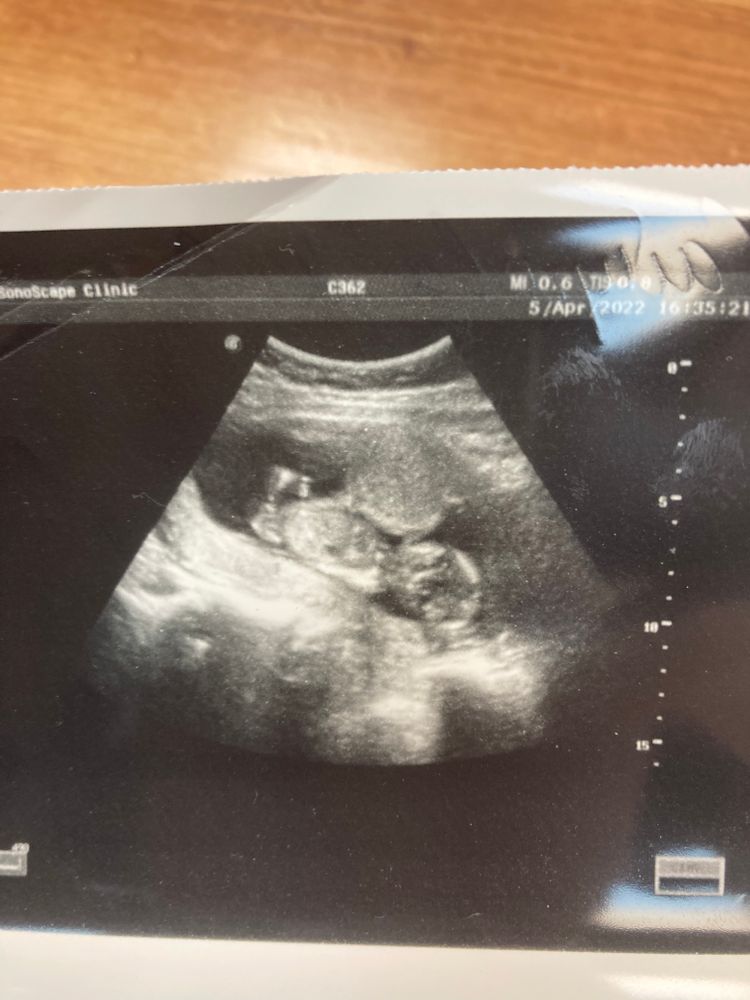

Kate, Изображение Это из городской больницы сегодняшнее узи

Извините, не совсем понимаю где миома на снимке? Просто у меня тоже крошечная и до 2ого скрининга ее пока не нашли. До Б видели. И то, что давит на малыша по центру, это что? У меня так же🙈Ох, я сапожок, ничего в этом УЗИ не понимаю.

Александра, вот на снимке как раз то,что они называют миомой и гипертонусом,но определится не могут